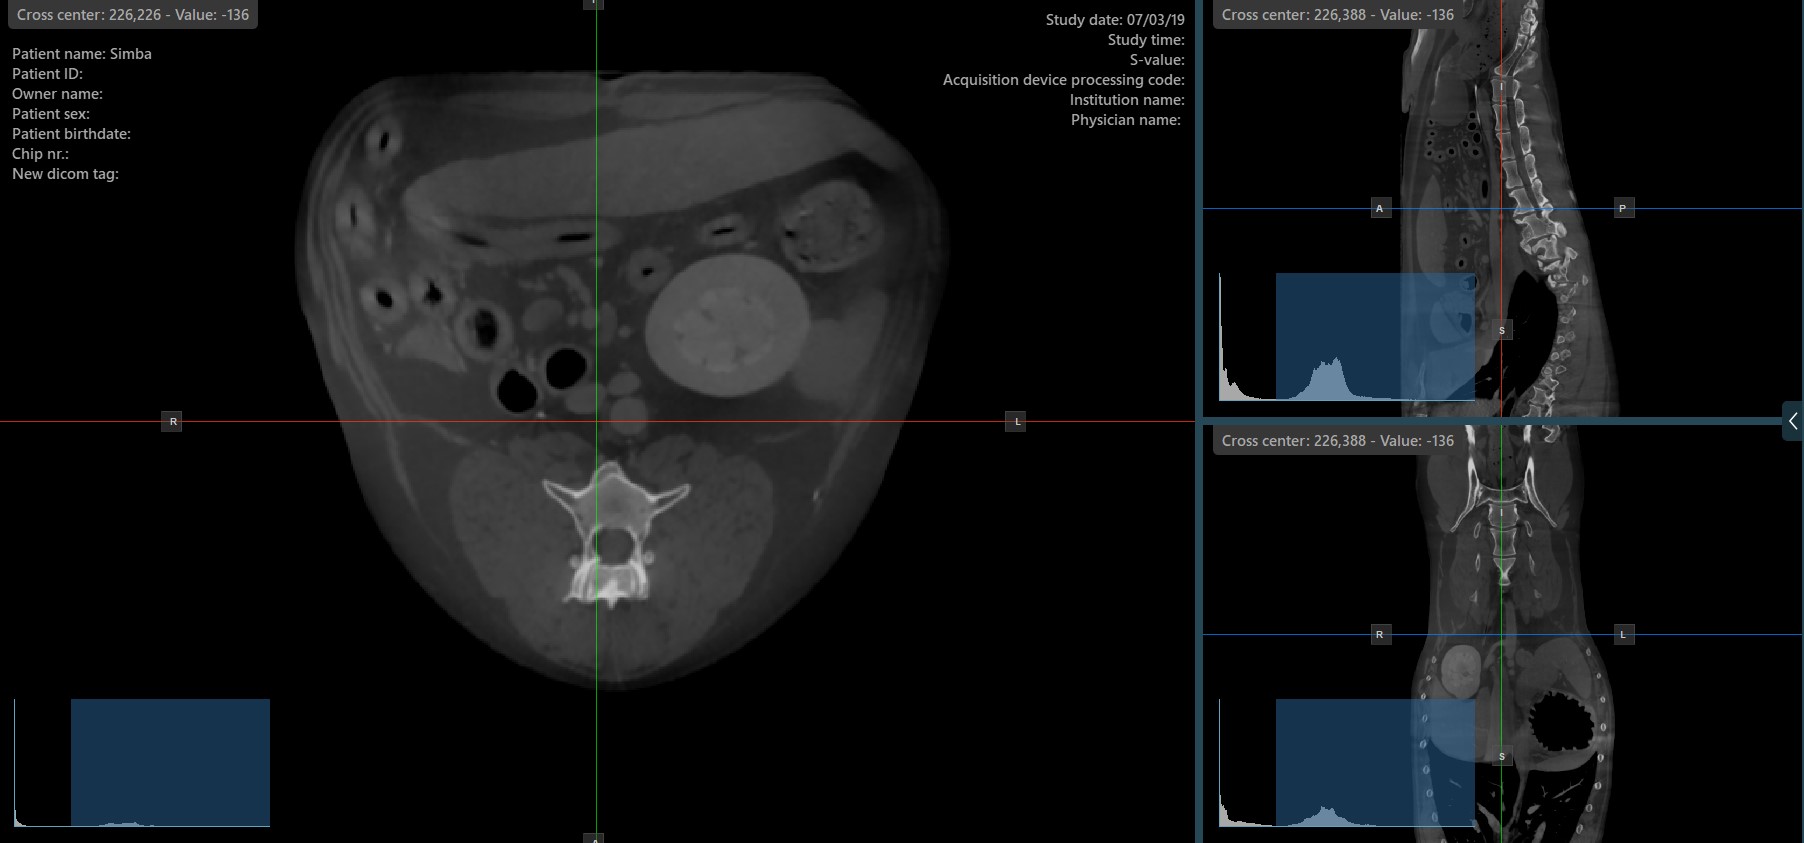

The slicers in MPR view show the intersections and orientation of the three image planes displayed in the active viewports. Users can modify the slicers and change the cross-sectional position of the slices based on the 3D volumetric data.

Each slicers is distinguished by their specific color, which representes the image plane:

The blue slicer marks the axial plane of the object (perpendicular to the ground)

The red slicer marks the coronal plane (parallel to the ground)

The green slicer marks the sagittal plane (perpendicular to the body)

By default, the slicers are visible on the top of the images. The corresponding icon in the left toolbar of the CT Viewer will be selected when the slicers are visible.